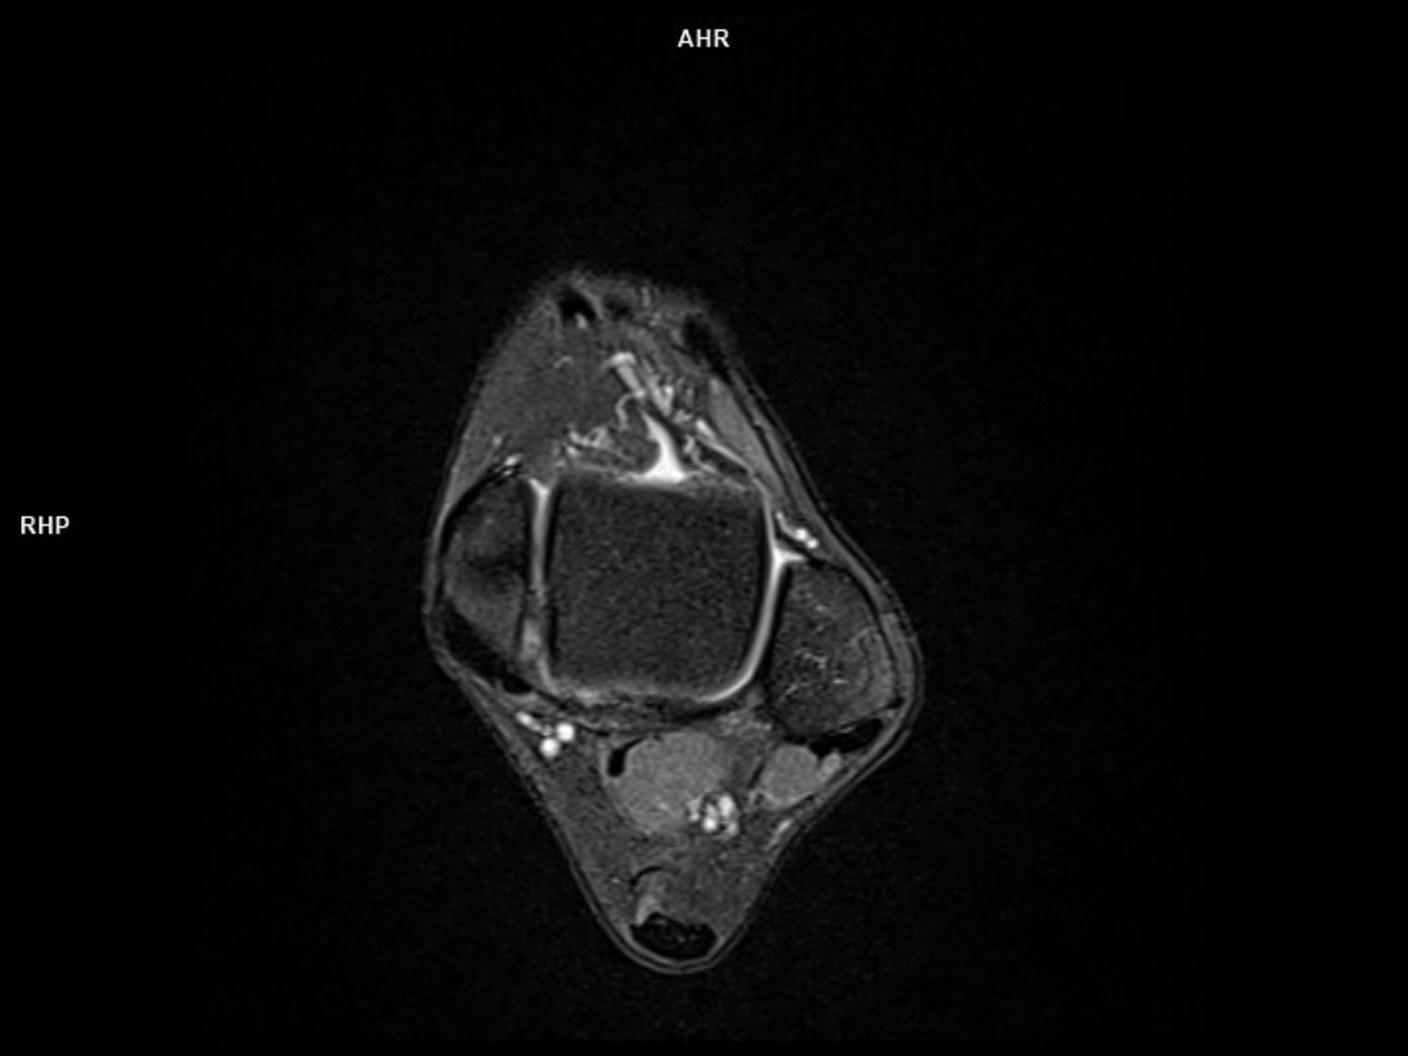

PD FS Tra-MAGNETOM Sola

PD FS Tra-MAGNETOM Sola/Coil-FootAnkle16/Resolution-352/Scan Time-1:45/Aceleration-s2